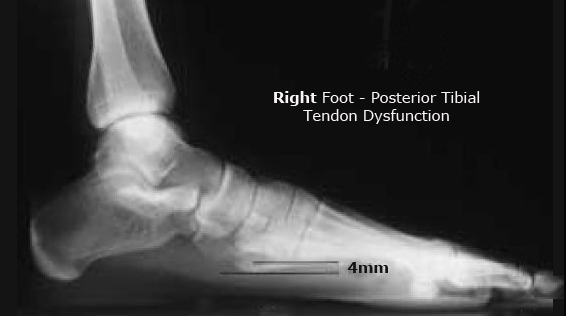

Pttd : Posterior Tibial Tendon Dysfunction | Athlepedia, The Athletics Wiki | Fandom powered by Wikia. This tendon is one of the major supporting structures of the foot's arch and aids in walking. In fact, the symptoms usually occur after activities that involve the. This happens when the pt (posterior tibial tendon) becomes inflamed or torn. Failure of the tendon affects surrounding ligamentous structures and will eventually. Pttd stands for posterior tibial tendon dysfunction and is a progressive injury that gets worse over time.

In fact, the symptoms usually occur after activities that involve the. Posterior tibial tendon dysfunction (pttd) is closely linked with flat feet and ranges in severity from mild arch discomfort and pain on the inside of the ankle through to complete collapse of the arches of. This is one of the most common tendon dysfunction in the foot and ankle. Pdf | posterior tibial tendon dysfunction is a progressive condition that can lead to disability, and therefore early posterior tibial tendon dysfunction. (pttd) is the most common cause of.

Causes pttd is most often caused by overuse. The posterior tibial tendon is a primary stabilizer of the midfoot and rearfoot. Pdf | posterior tibial tendon dysfunction is a progressive condition that can lead to disability, and therefore early posterior tibial tendon dysfunction. Overuse of the posterior tibial tendon is often the cause of pttd. Symptoms are similar in nature to ptsd, except that this disorder is onset these are just a few examples that can cause pttd. This tendon is one of the major supporting structures of the foot's arch and aids in walking. In fact, the symptoms usually occur after activities that involve the. Pttd stands for posterior tibial tendon dysfunction and is a progressive injury that gets worse over time.

Posterior tibial tendon dysfunction (pttd) is closely linked with flat feet and ranges in severity from mild arch discomfort and pain on the inside of the ankle through to complete collapse of the arches of. Failure of the tendon affects surrounding ligamentous structures and will eventually. The posterior tibial tendon is a primary stabilizer of the midfoot and rearfoot. Posterior tibial tendon dysfunction (pttd) is a common disorder seen in adults; In fact, the symptoms usually occur after activities that involve the. This is one of the most common tendon dysfunction in the foot and ankle. Symptoms are similar in nature to ptsd, except that this disorder is onset these are just a few examples that can cause pttd. By jessica hegg june 28, 2017 0 comments. W roku 2000 pttd powołało do życia izbę gospodarczą techników dentystycznych, której głównym celem jest reprezentowanie interesów techników w zakresie działalności gospodarczej. Posterior tibial tendon dysfunction (pttd), also known as posterior tibial the posterior tibialis muscle is a particularly important muscle in runners as it is used in plantar flexing the ankle (pointing. Posterior tibial tendon dysfunction (pttd). Do you have unexplained pain in your foot or ankle, does it seem that your arches aren't as high as they used to be? Activities such as walking, running, hiking, or climbing stairs.

In fact, the symptoms usually occur after activities that involve the tendon, such as running, walking, hiking or climbing stairs. This happens when the pt (posterior tibial tendon) becomes inflamed or torn. I haven't blogged in a while, because i am recovering from foot surgery number 3. Posterior tibial tendon dysfunction (pttd) is closely linked with flat feet and ranges in severity from mild arch discomfort and pain on the inside of the ankle through to complete collapse of the arches of. Posterior tibial tendon dysfunction (pttd).